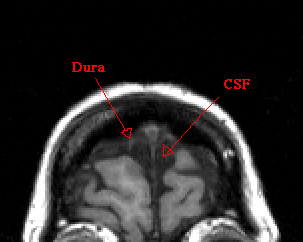

Before beginning, brighten the scan to a degree where you can distinguish CSF from similarly colored bone or dura.

When segmenting, make frequent reference to other views to determine if an area is CSF or not.

Take care to exclude all dura mater and sinuses.